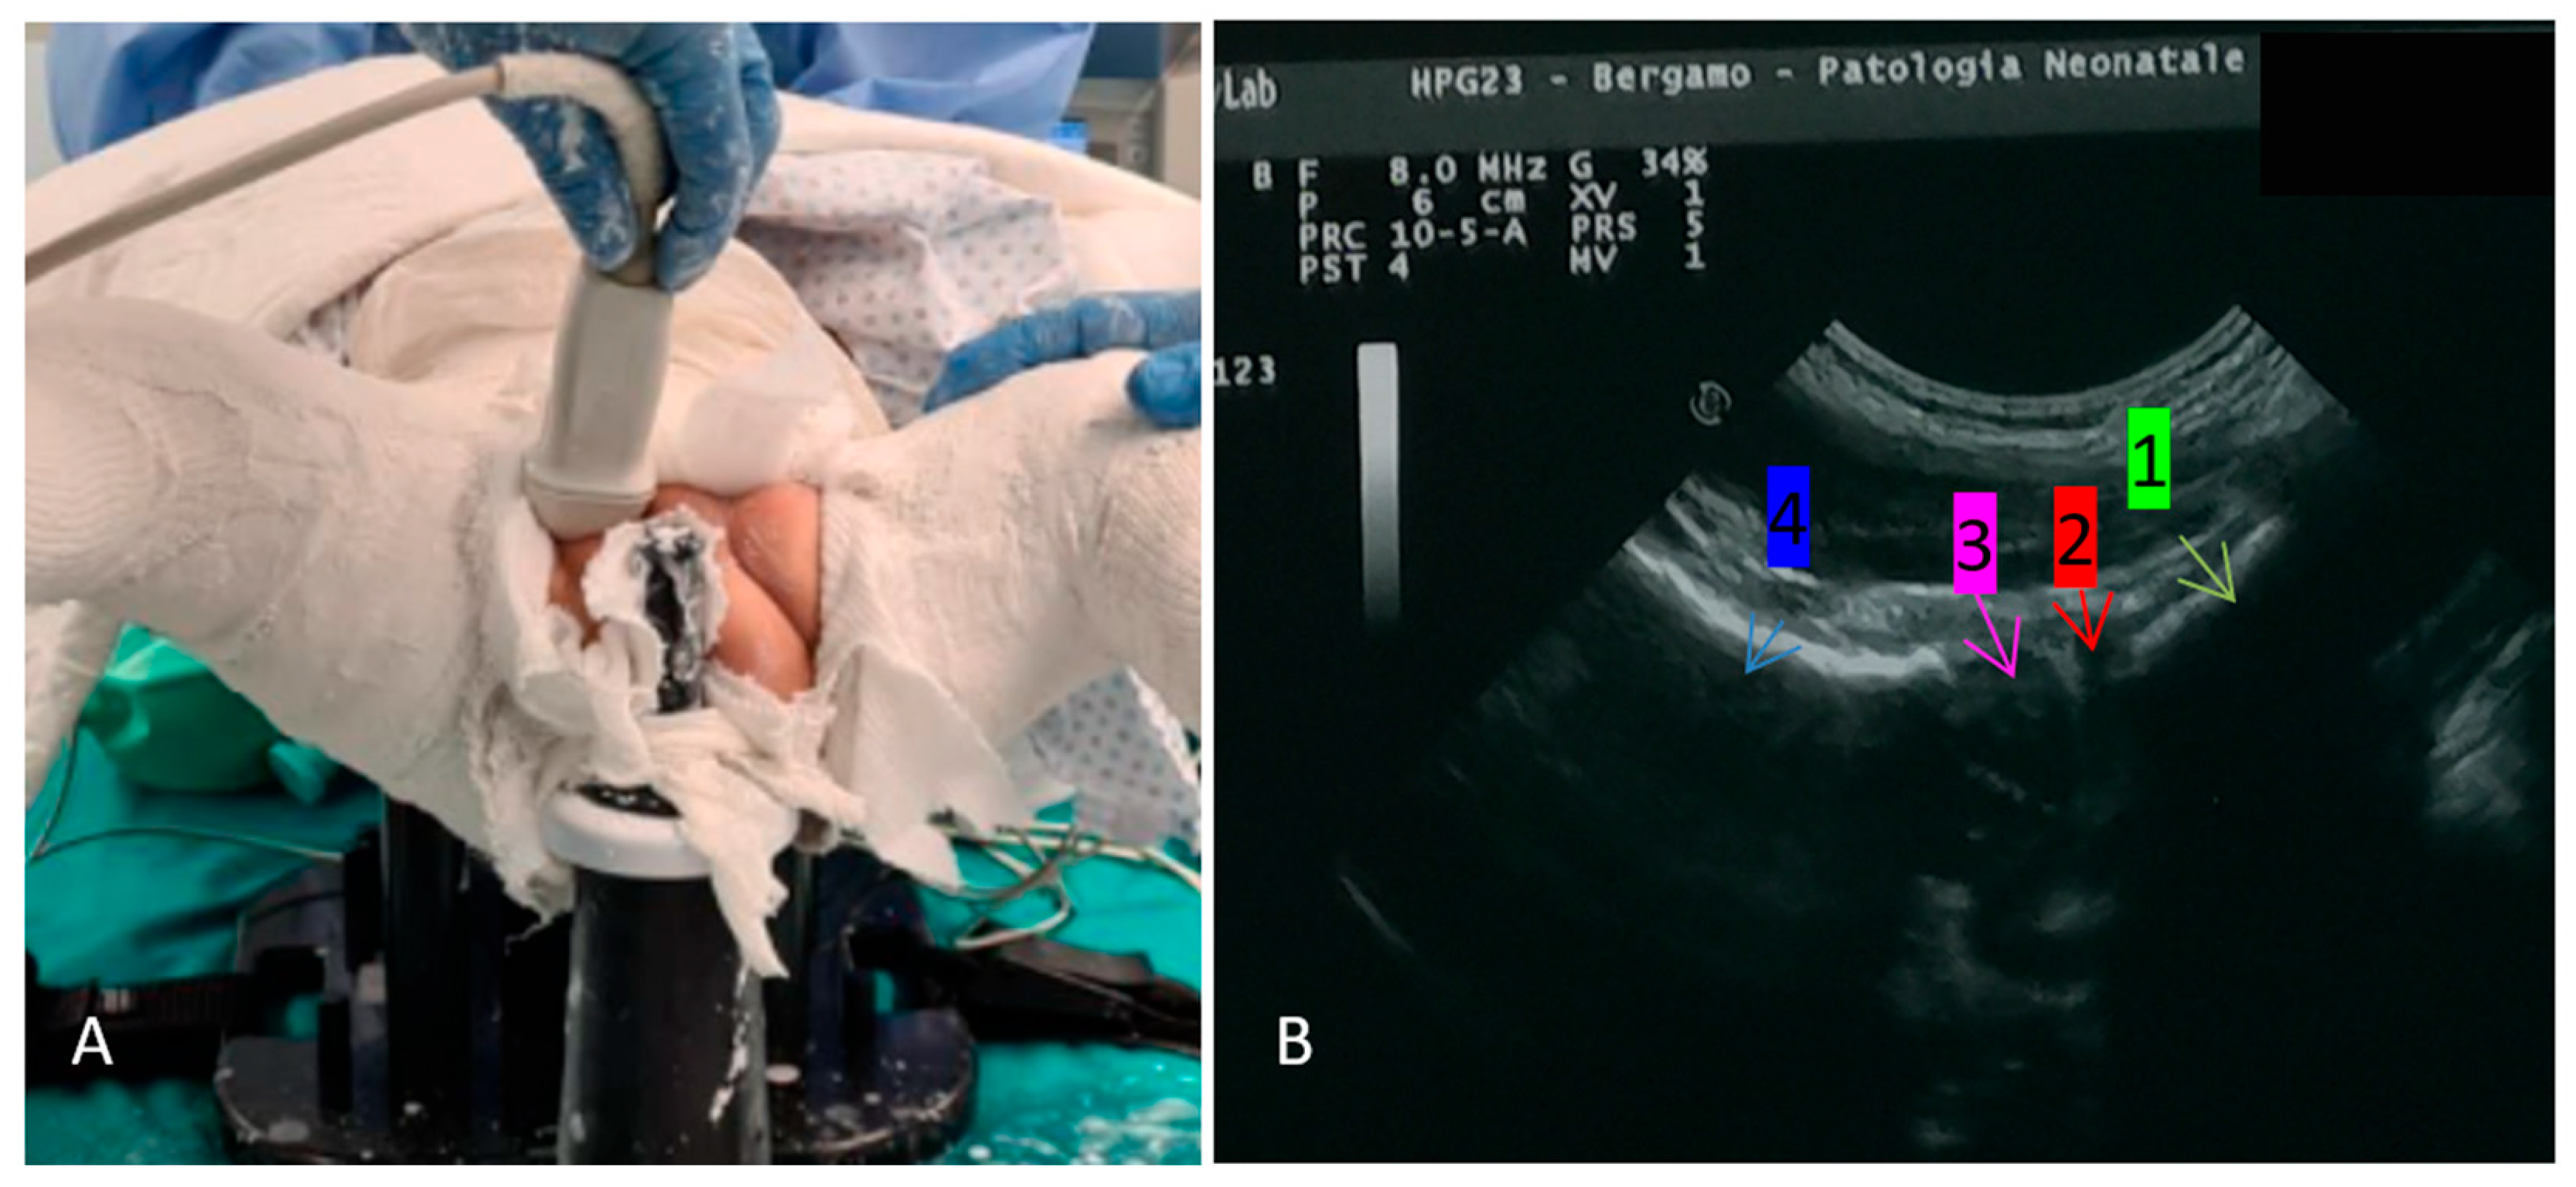

- Eberhardt, O.; Zieger, M.; Wirth, T.; Fernandez, F.F. Determination of femoral head position with transinguinal ultrasound in DDH treatment. Z. Orthop. Unfall. 2009, 147, 727–733. [Google Scholar] [CrossRef] [PubMed]

- van Douveren, F.Q.M.P.; Pruijs, H.E.H.; Sakkers, R.J.B.; Nievelstein, R.A.J.; Beek, F.J.A. Ultrasound in the management of the position of the femoral head during treatment in a spica cast after reduction of hip dislocation in developmental dysplasia of the hip. J. Bone Jt. Surg. Ser. B 2003, 85, 117–120. [Google Scholar] [CrossRef]

- Beek, F.J.A.; Nievelstein, R.J.; Pruijs, H.E.; De Jong, P.A.; Sakkers, R.J.B. Transinguinal sonographic determination of the position of the femoral head after reposition and follow-up in a spica cast. Pediatr. Radiol. 2010, 40, 1794–1799. [Google Scholar] [CrossRef] [PubMed]